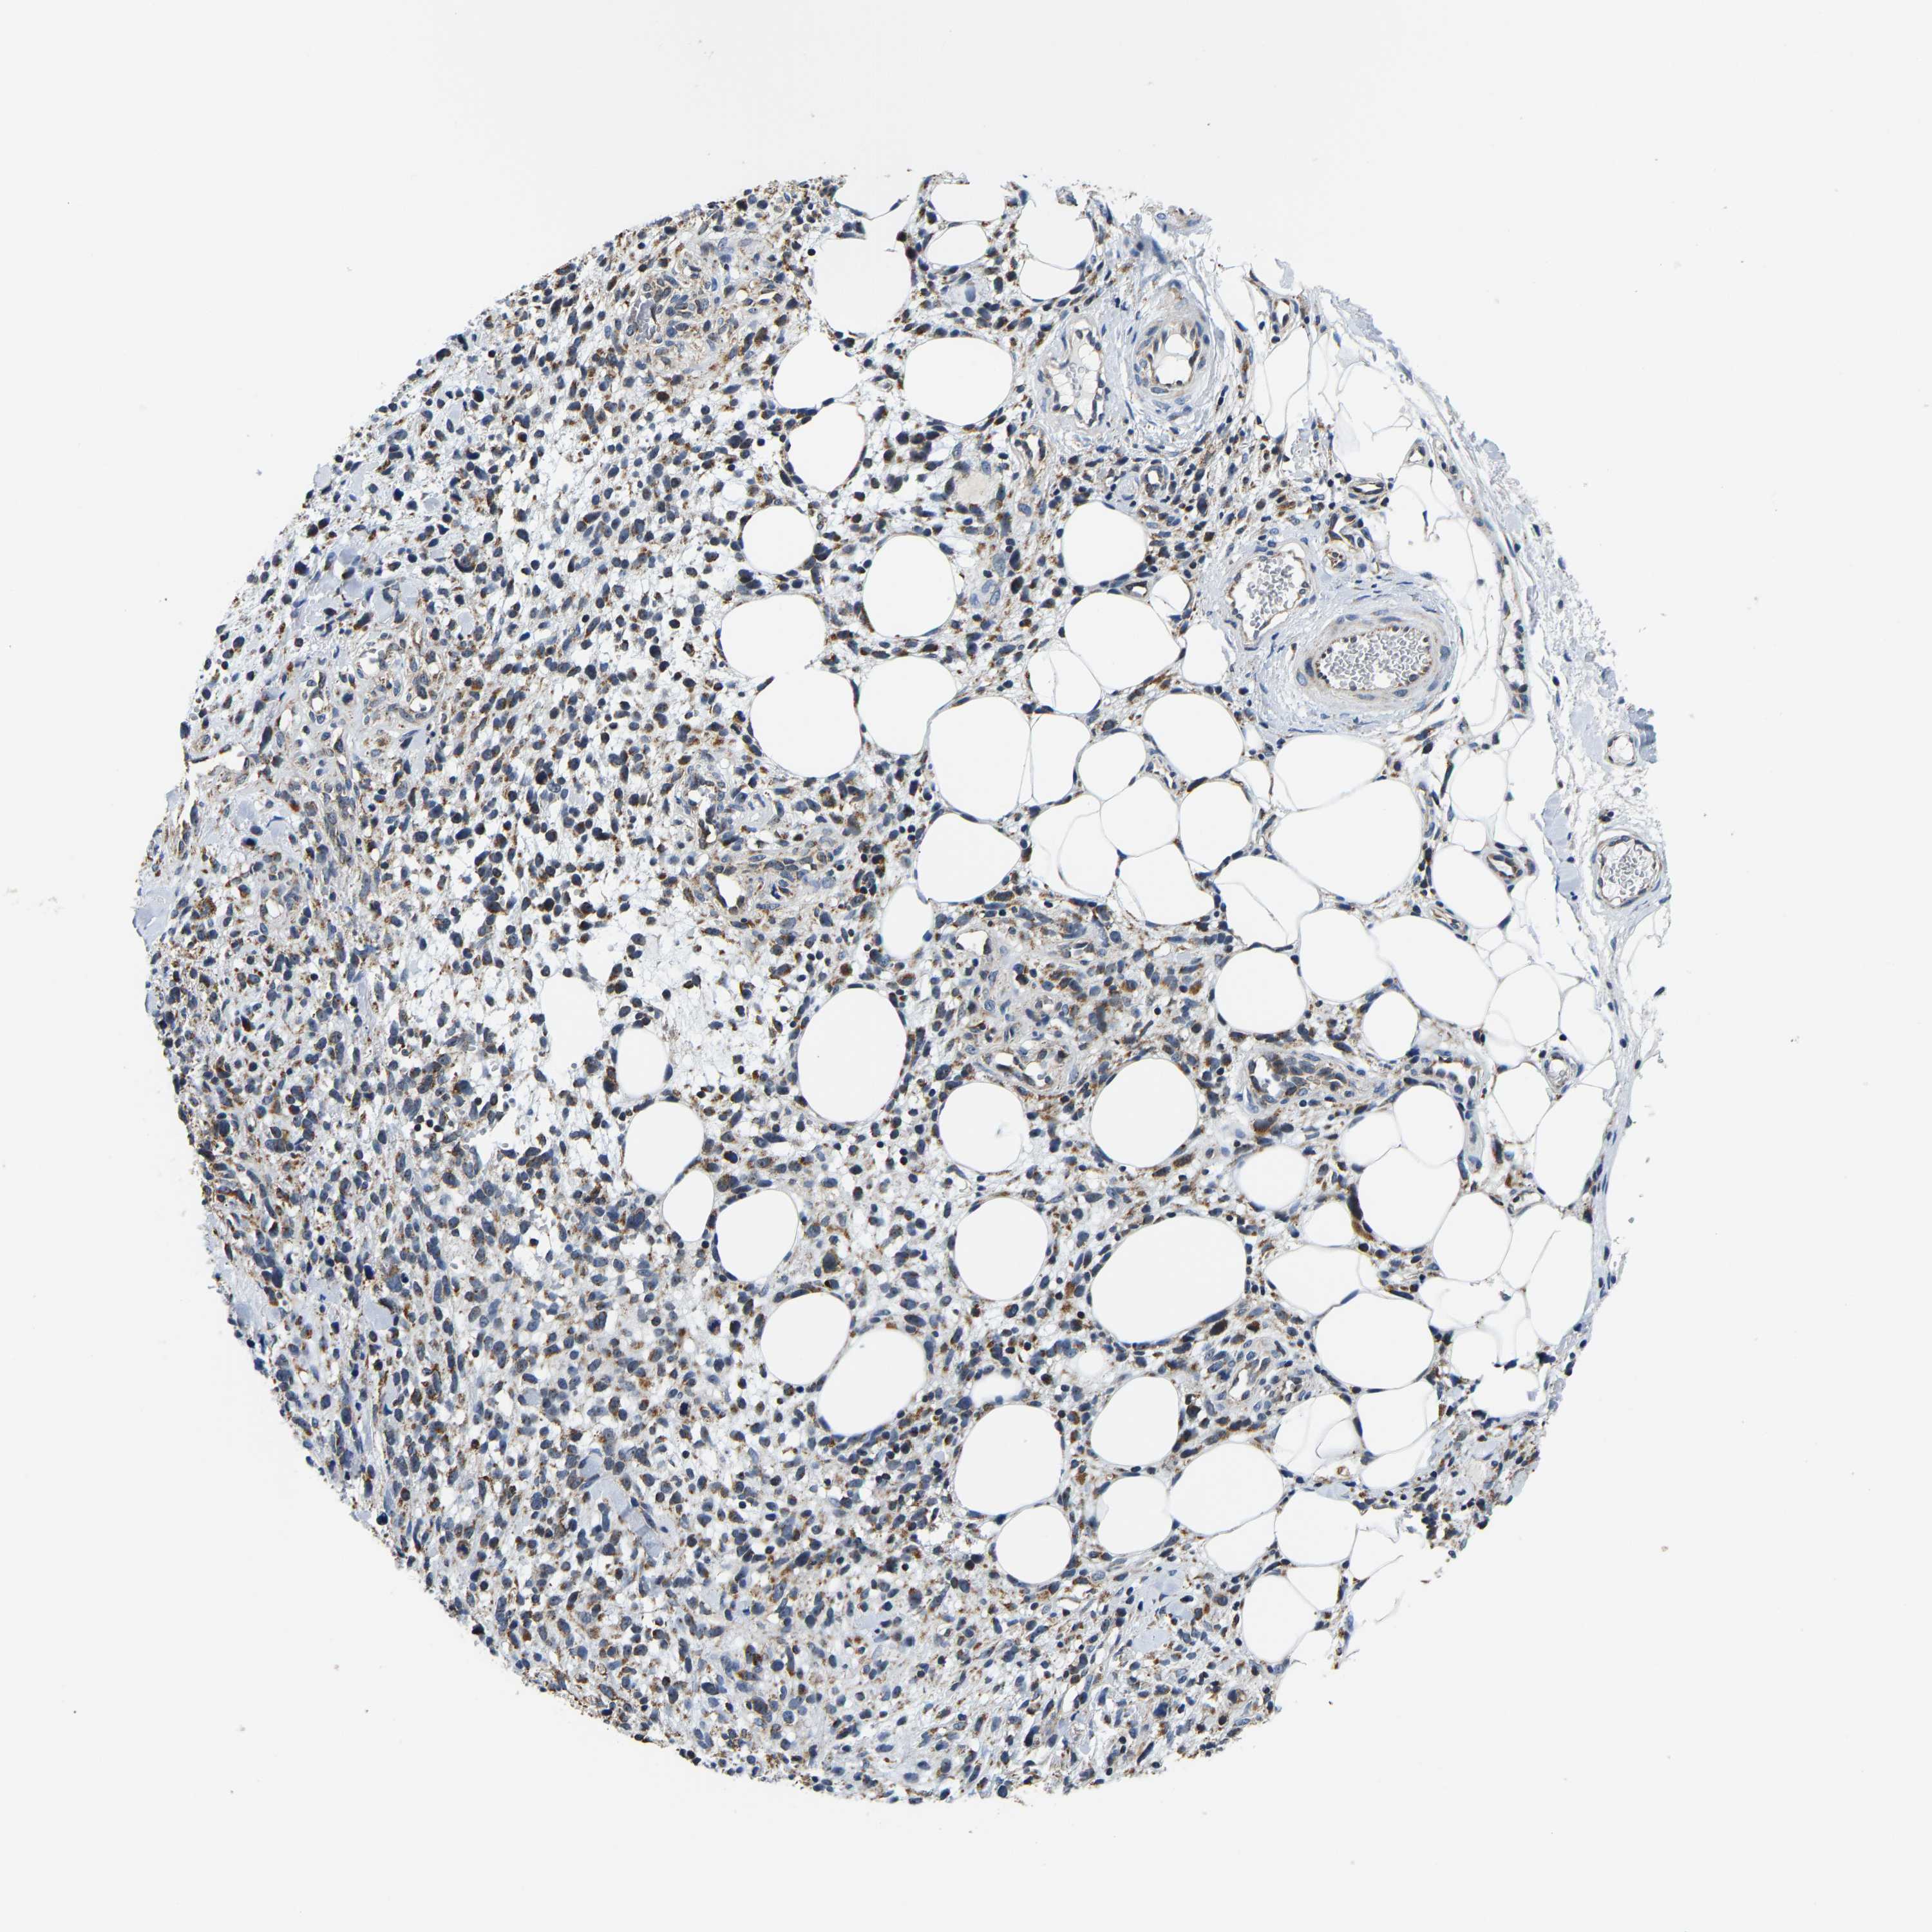

MELANOMA - Protein expressioni

A mouse-over function shows sample information and annotation data. Click on an image to view it in a full screen mode. Samples can be filtered based on level of antibody staining by selecting one or several of the following categories: high, medium, low and not detected. The assay and annotation is described here.

Note that samples used for immunohistochemistry by the Human Protein Atlas do not correspond to samples in the TCGA dataset.

Antibody stainingi

Antibody staining in the annotated cell types in the current human tissue is reported as not detected, low, medium, or high, based on conventional immunohistochemistry profiling in selected tissues. This score is based on the combination of the staining intensity and fraction of stained cells.

Each image is clickable and will lead to virtual microscopy that enables deeper exploration of all samples and also displays staining intensity scores, fraction scores and subcellular localization as well as patient and tissue information for each sample.

Antibody HPA020266

Antibody HPA020268

Staining

High

Medium

Low

Not detected

Intensity

Strong

Moderate

Weak

Negative

Quantity

>75%

75%-25%

<25%

None

Location

Nuclear

Cytoplasmic/membranous

Cytoplasmic/membranous,nuclear

Malignant melanoma, NOS

Malignant melanoma, Metastatic site